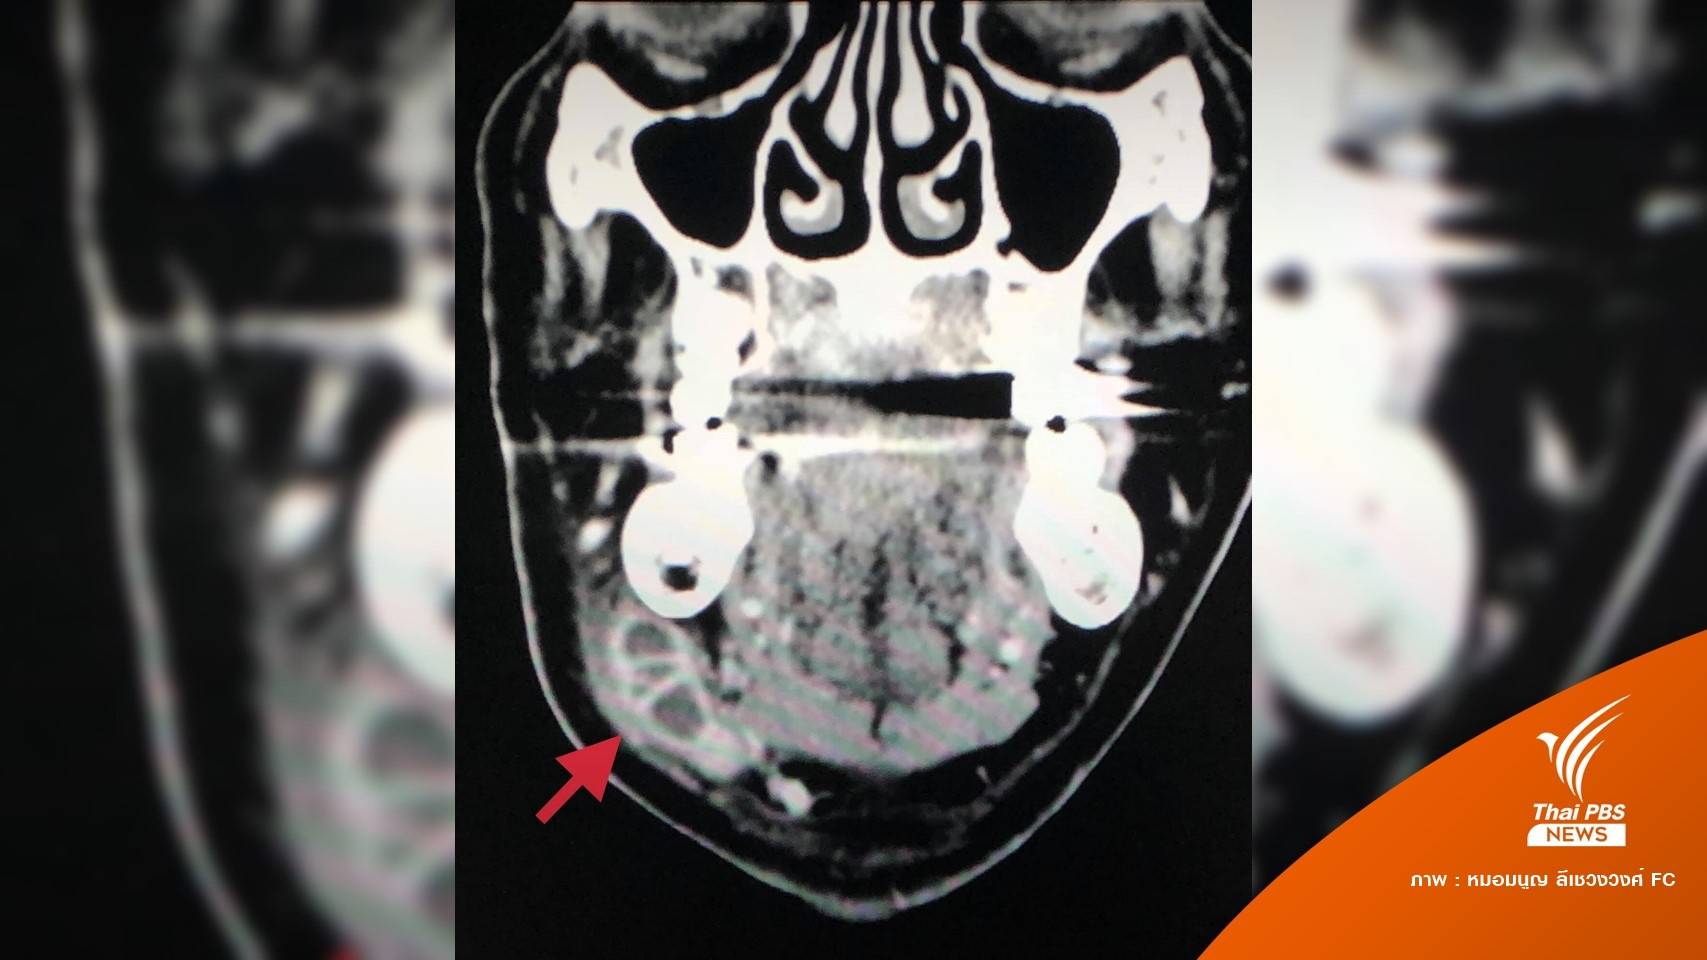

ทั้งนี้พบเคสผู้ป่วยหญิงไทยอายุ 66 ปี เป็นโรคความดันโลหิตสูง มาพบแพทย์ด้วยอาการบวม เจ็บใต้คางข้างขวา 6 วัน ไม่มีไข้ ไม่เบื่ออาหาร น้ำหนักไม่ลด ไม่ไอ ไม่เจ็บฟันให้ยาปฏิชีวนะกินครบ 7 วันไม่ดีขึ้น ก้อนใต้คางโตขึ้น ตรวจร่างกาย ไม่มีไข้ ผิวหนังบริเวณใต้คางไม่แดง ไม่ร้อน คลำได้ก้อนใต้คางข้างขวา เจาะเลือดเม็ดเลือดขาวปกติ เอกซเรย์ปอดปกติ ได้ทำคอมพิวเตอร์สแกนของลำคอพบก้อนขนาด 2.3 × 1.6 × 2.1 เซนติเมตร ที่บริเวณใต้คางข้างขวา สงสัยเป็นฝีของต่อมน้ำลาย

จากนั้นเจาะหนองจากฝี ของต่อมน้ำลาย ส่งตรวจย้อมเชื้อ AFB และตรวจหายีนของเชื้อวัณโรคให้ผลบวก ผลเพาะเชื้อขึ้นเชื้อวัณโรค Mycobacterium tuberculosis กำลังรอผลการทดสอบความไวของเชื้อวัณโรคต่อยา สรุปว่าผู้ป่วยคนนี้เป็นวัณโรคของต่อมน้ำลาย ได้ให้ยารักษาวัณโรค อาการบวมและเจ็บน้อยลง